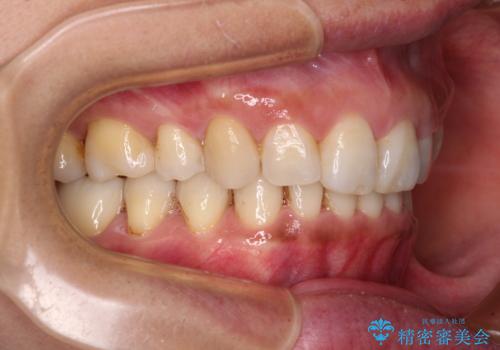

抜歯矯正の後戻りでできたスペース インビザライン矯正とセラミック治療

- 以前行った抜歯矯正が後戻りし、開いてしまったスペースが気になるとのことで来院された患者様です。

インビザラインを用いて開いてしまったスペースと前歯のデコボコを改善することとしました。

矯正治療後には気になっていた銀歯をセラミッククラウンやセラミックインレーにて治療することとしました。

上顎前歯を左右対称となるように歯列を整えたいとのことでしたが、すり減って形態が大きく異なっていたため、できる範囲での仕上がりとなりました。